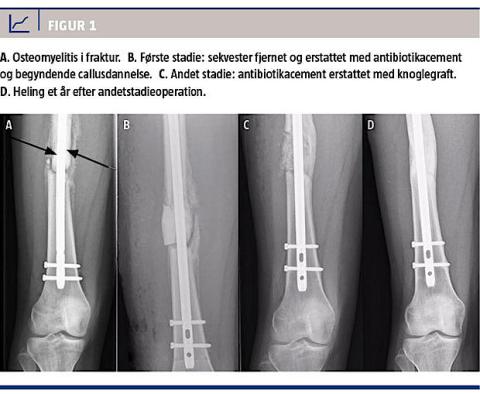

I efterforløbet var der initialt fremgang, men to måneder postoperativt sås der infektionstegn, og på en røntgenoptagelse konstaterede man osteomyelitis med manglende heling og tegn på sekvesterdannelse (Figur 1A). Patienten blev reopereret med anvendelse af Masquelets teknik.

Under det første indgreb fjernedes det indsatte marvsøm, knogle og bløddele blev revideret grundigt, inficeret væv blev fjernet, et 45 mm langt knoglestykke blev excideret, og der blev skyllet grundigt. Frakturen stabiliseredes med et nyt femurmarvsøm, og knogledefekten blev fyldes med antibiotikacement (Figur 1B).

På dette tidspunkt var der dannet en velvaskulariseret membran omkring den indsatte cement-spacer. Der blev lavet en forsigtig incision i membranen, cement-spacer’en blev fjernet, og knogleenderne blev inforeret. Til sidst blev der ilagt knogleallograft samt membran, og såret blev lukket (Figur 1C). Patienten blev mobiliseret med fuld belastning og fulgt ambulant.

Et år efter den sidste procedure var knoglegraften fuldstændig inkoopereret og omdannet til rørknogle (Figur 1D). Det indsatte marvsøm kunne

fjernes, og patienten, som nu var 17 år, var i velbefindende og kunne støtte fuldt på benet. Ved afslutningen af behandlingen blev det vurderet, at patienten havde egal benlængde, og hun var velfungerende i hverdagen, hvor hun var i stand til at dyrke motion i form af løb.